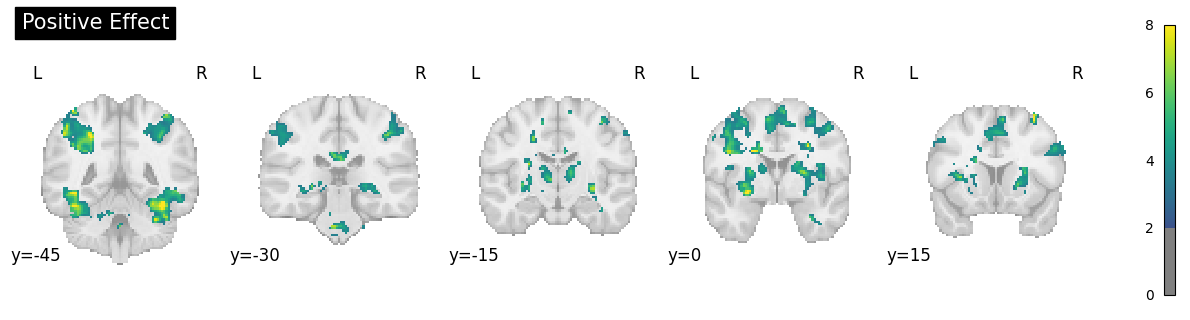

con_0005: Positive effect

con_0006: Positive Effect F>S

con_0007: Positive Effect S>U

con_0008: Positive Effect of rep1>rep2

con_0009: Positive Interaction Face (F/S) x Rep

con_0010: Positive Interaction Face (S/U) x Rep

wf_2ndlevel_onesample = Workflow(name='level2_spm_1sample', base_dir=experiment_dir)

wf_2ndlevel_onesample.config["execution"]["crashfile_format"] = "txt"

contrast_id = [5, 6, 7, 8, 9, 10] #contrasts con_0005 to con_0010

l2source = Node(DataGrabber(infields= ['con'], outfields=['contrasts']), name='l2source')

l2source.inputs.sort_filelist = True

l2source.inputs.base_directory = opj(experiment_dir, 'level1_spm_results')

l2source.inputs.template = '*'

l2source.inputs.field_template = dict(

contrasts = '*/con_%04d.nii'

)

# iterate over all contrast images

l2source.iterables = [('con', contrast_id)]

# OneSampleTTest Design

onesamplettestdes = Node(interface=spm.OneSampleTTestDesign(), name="onesampttestdes")

wf_2ndlevel_onesample.connect([(l2source, onesamplettestdes, [('contrasts', 'in_files')])])

# EstimateModel - estimates the model

l2estimate = Node(spm.EstimateModel(estimation_method={'Classical':1}), name='level2estimate')

# EstimateContast - estimates group contrast

l2conestimate = Node(spm.EstimateContrast(group_contrast=True), name = 'level2conestimate')

con_1= ['Group', 'T', ['mean'], [1]]

#con_2= ['Group', 'F', [con_1]] # if an F contrast is also wanted

l2conestimate.inputs.contrasts = [con_1] # con_2, include in list if wanted

# Threshold - thresholds contrasts

level2thresh = Node(spm.Threshold(contrast_index=1,# which contrast in the SPM.mat to use --> here set for con_1: T stat

use_topo_fdr=True, # whether to use FDR over cluster extent probabilities

use_fwe_correction=False, # whether to use FWE (Bonferroni) correction for initial threshold

extent_threshold=0, # minimum cluster size in voxels

height_threshold=0.005, # value for initial thresholding (defining clusters) - voxelwise

height_threshold_type='p-value',

extent_fdr_p_threshold=0.05), # p threshold on FDR corrected cluster size probabilities

name='level2thresh')

wf_2ndlevel_onesample.connect([(onesamplettestdes, l2estimate, [('spm_mat_file', 'spm_mat_file')]),

(l2estimate, l2conestimate, [('spm_mat_file', 'spm_mat_file'),

('beta_images', 'beta_images'),

('residual_image', 'residual_image')]),

(l2conestimate, level2thresh, [('spm_mat_file', 'spm_mat_file'),

('spmT_images', 'stat_image')])

])

datasink_2nd = Node(DataSink(), name='datasink_2nd')

datasink_2nd.inputs.base_directory=opj(experiment_dir, 'level2_spm_results_1sample')

wf_2ndlevel_onesample.connect([(l2conestimate, datasink_2nd, [('spm_mat_file', '2ndLevel.@spm_mat'),

('spmT_images', '2ndLevel.@T'),

('con_images', '2ndLevel.@con')]),

(level2thresh, datasink_2nd, [('thresholded_map',

'2ndLevel.@threshold')])

])

#replace _con_ with con